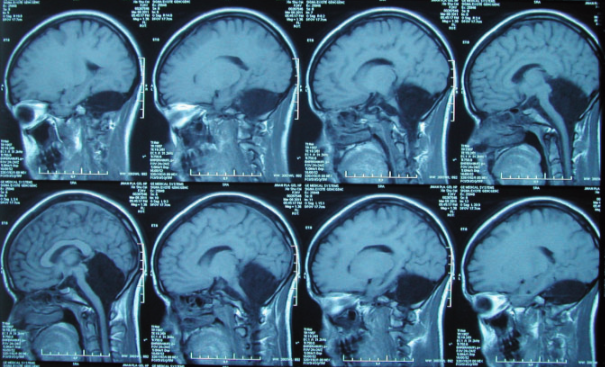

En 2014, una mujer de 24 años fue admitida en un hospital de China con síntomas como mareos, dificultad para caminar de manera estable durante más de 20 años, náuseas y vómitos durante aproximadamente un mes. Sus padres no tenían antecedentes de trastornos neurológicos, y sus cuatro hermanas y un hermano se describían como neurológicamente normales.

Asimismo, la paciente estaba casada y tuvo a su hija con un embarazo y parto sin complicaciones. No obstante, tras los análisis de tomografía computarizada, los resultados demostraron ausencia de tejido cerebeloso (Yu et al., 2015).